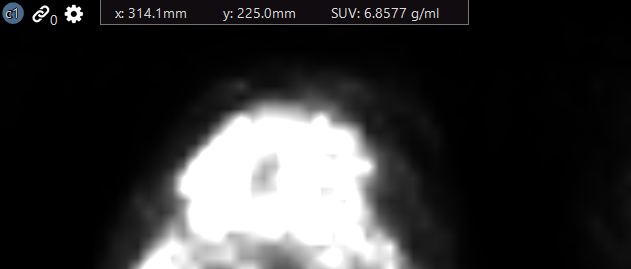

Pixel Position and Value

The viewer displays the position of a select image pixel and it's associated value.

Pixel Position

To display the position of a select pixel:

From the View menu, select Show Pixel Position

Position the mouse over a position in the image of the selected image frame.

The x and y coordinates of the pixel at the cursor's hot spot is displayed as text fields along the top of the image frame.

To display the value of a selected pixel:

From the View menu, select Show Pixel Value.

Position the mouse over a position in the image of the selected image frame.

The pixel value (level) at the cursor's hot spot is displayed in a text field along the top of the image frame.

Standard Uptake Value (SUV)

To display the standard update value (SUV):

From the View menu, select Show Pixel Value.

Position the mouse over a position in the image that contains the required information needed to calculate the SUV value. Be aware, the software automatically calculates the value if the required data is present. If it is not present, the pixel value is displayed in place of the SUV.

The SUV at the cursor's hot spot is displayed in a text field along the top of the image frame.